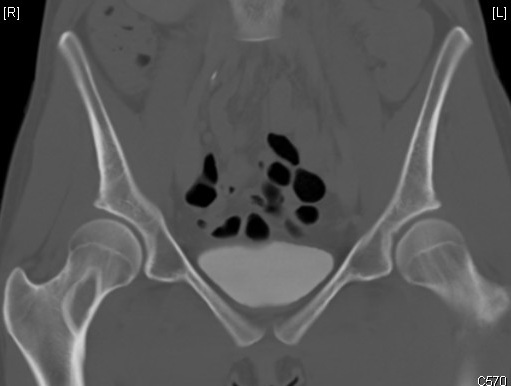

Dysplasie fibreuse du col fémoral droit, asymptomatique, chez une jeune fille